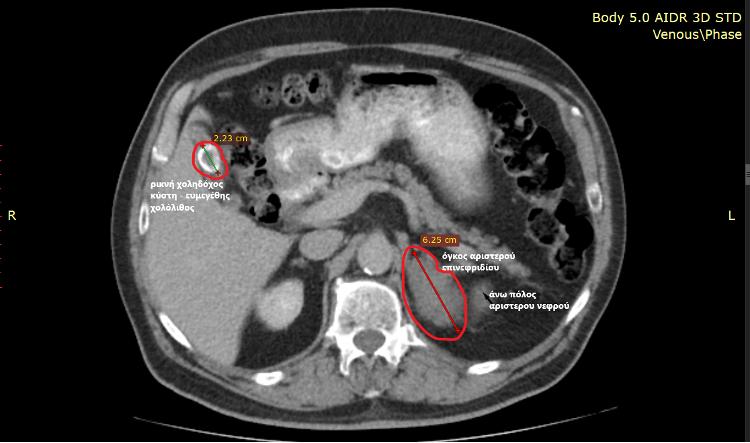

Η επέμβαση αφορούσε ασθενή 70 ετών με αυξημένο δείκτη μάζας σώματος (BMI 40,3) και τριπλή παθολογία που συνίστατο σε:

- ευμεγέθη όγκο αριστερού επινεφριδίου πάνω από 6,5 εκ και πιθανή κακοήθεια

- χολολιθίαση με υποτροπιάζουσες χολοκυστίτιδες